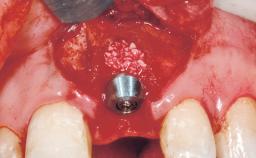

Immediate Flapless Placement of an Implant in a Maxillary Left Central Incisor Site

A 42-year-old female patient was referred to our clinic at the School of Dentistry of the University of São Paulo in November 2004, presenting a deficient restoration in the upper left central incisor. The clinical examination revealed no gingival retraction or any signs of gingival inflammation and, therefore, previous periodontal treatment was not considered. The patient presented a high lip line at full smile and a thin tissue biotype. This combination characterized a high-risk situation from an anatomic point of view, which required careful preoperative planning and cautious surgical execution.

Placement Protocol Immediate implant placement

Tooth Site Maxillary incisor or canine

Socket Morphology Single-root socket

Socket Integrity Sufficient, with intact bone walls

Bone Volume Sufficient, with intact walls